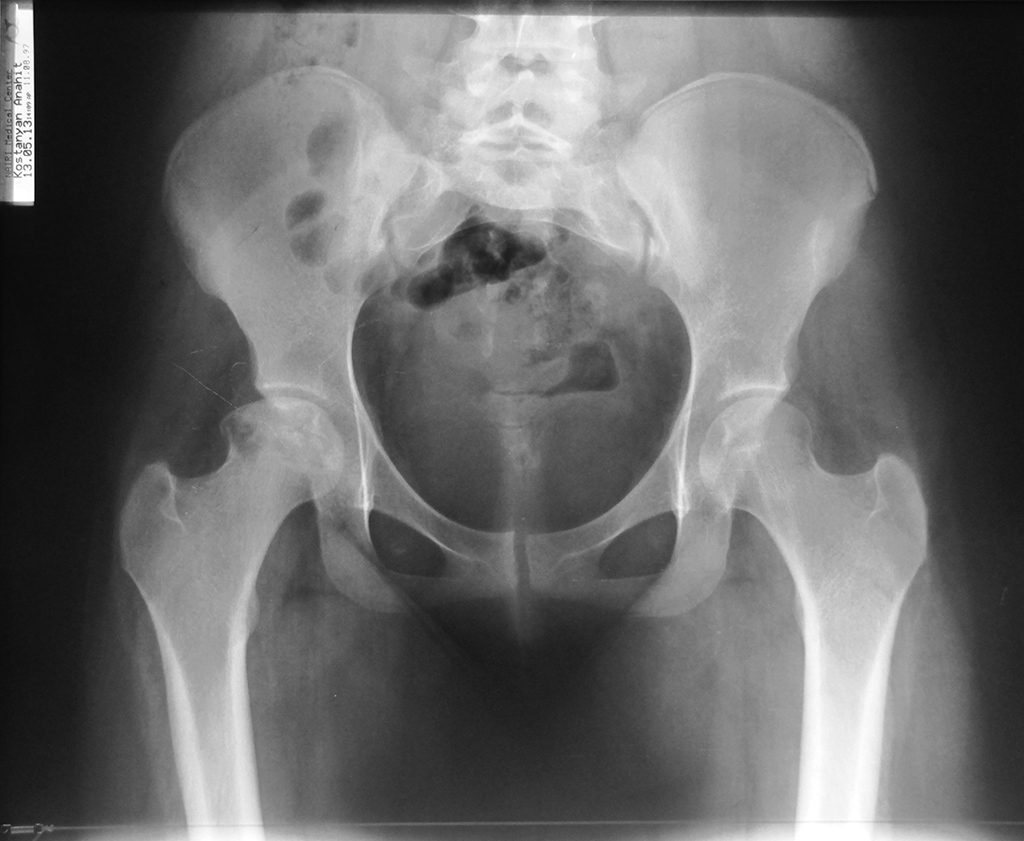

В пользу АНГБК говорят многие факторы: пол (нехарактерен для Пертеса, впрочем как и для и АНГБК), возраст, сопутствующая патология и т.п. Однако за болезнь Пертеса - течение процесса, завершившиеся фактически восстановлением формы головки и конгруэнтности суставной щели.

На рентгенограммах, вряд ли кто-то оспорит, динамика положительная. А как с клинической картиной? Если она тоже положительная, возможно не стоит спешить с эндопротезированием?

Ограничение отведения и частично боли могут быть обусловлены потерей офсета головочно-шеечного соединения и изменения его формы. При ремоделировании головки, восстановления ее сферичности и упомянутого офсета проблема ограничения отведения может быть решена. Сложно сказать по представленным рентгенограммам насколько ФАИ выражен в других отделах, но передний доступ и артроскопия ТБС едва ли восстановят в полной мере офсет верхнего и заднего отделов головки. Считаю, в данном случае оптимальней хирургический вывих.

Но настораживает выраженный остеопороз головки под нагрузочной зоной головки. После ремоделирования она может просто потерять латеральную опору, снова провалиться и о спасении головки и сустава можно забыть. Вот тогда придется точно заняться подбором эндопротеза.

> На рентгенограммах, вряд ли кто-то оспорит, динамика положительная. А как с клинической картиной? Если она тоже положительная, возможно не стоит спешить с эндопротезированием?

- насколько я понял из дат, "промятая" головка это уже в 14 году

Отправитель: Ильдар Ахтямов 27 Октябрь 2014, 11:35

Антон, боюсь, что твоя трактовка снимков ошибочна. Если взглянуть на даты рентгенограмм (13 и 14 год), то складывается картина развивающегося процесса. Произошла секвестрация. Это не Пертеса, а АНГБК. Наропинотерапия хороша до коллапса хрящевого слоя, но можно попробовать. В данном случае все средства хороши, однако боюсь, что все закончится тотальным протезированием с короткой ножкой и парой керамика-керамика. АИФ

Извините за ошибку, на устройстве фото снимков отобразилось в обратном хронологическом порядке. Конечно это АНГБК в предпоследней стадии. Речи о сохранении головки уже не идет.((((

No, it;s been deteriorating! (2013 - 2014).